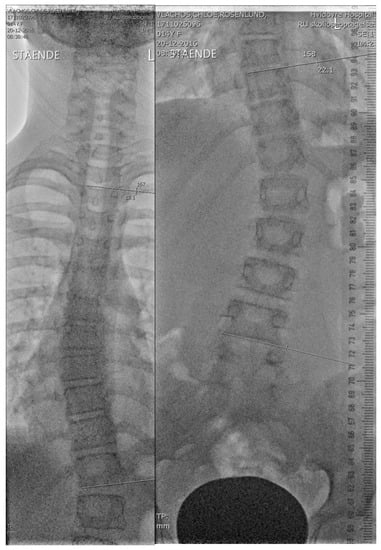

2.2. Initial in-Brace Radiographs